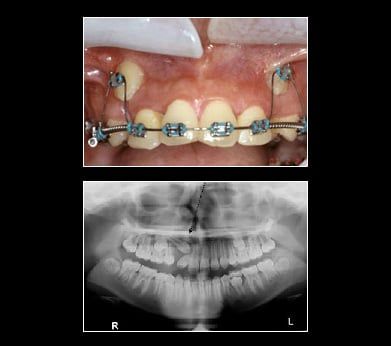

Impacted Canine

Canine teeth are also commonly referred to as cusped or "eye teeth" since the teeth align under your eyes. You should have two canines in both your upper and lower jaw. They are the strongest teeth you have, used for tearing into your most meaty meals. Because of this need for strength, your canines have the longest roots of all your teeth. They are an essential part of your bite and balanced smile for two main reasons:

Your canine teeth are generally some of the last teeth to erupt. Occasionally they do not erupt. The two most common reasons are:

The fact that teeth don't always come in like they're supposed to highlights the need for regular dental visits when young teeth are developing. If you suspect your child has impacted canines, don't hesitate to make an appointment with Dr. Peter Russo. With regular dental visits, x-rays and examinations, the problem of impacted canines can be found out early when treatment is easier. If you are an adult and your canines have not erupted Dr. Peter Russo can help. Set an appoint today for an x-ray and consultation. Your smile is up there waiting for you.

Treatment for Impacted Canines

After assessing your situation, Dr. Peter Russo will devise a plan to make room for your canines. Will a typical oral surgery and the assistance of an orthodontist your canine will find their way into their proper place over time.